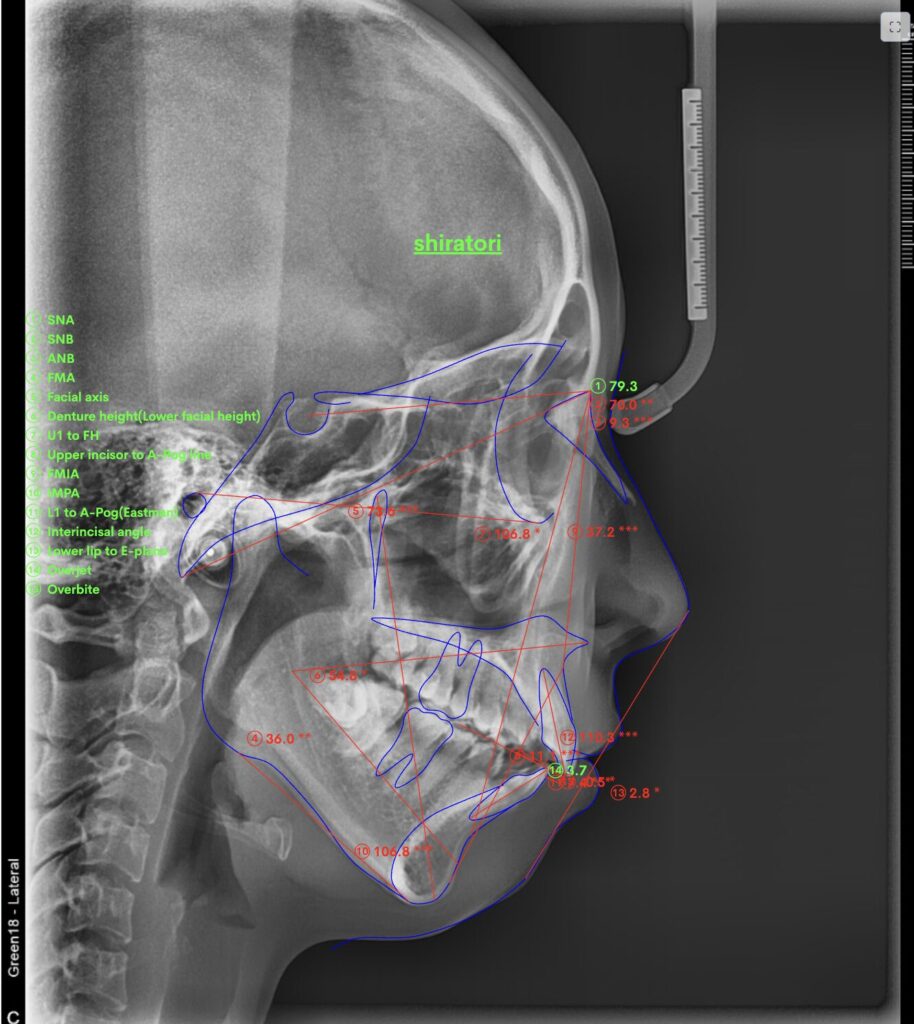

セファロX線写真と分析

CT写真を活用し、骨格的に無理ないようにたてた治療計画